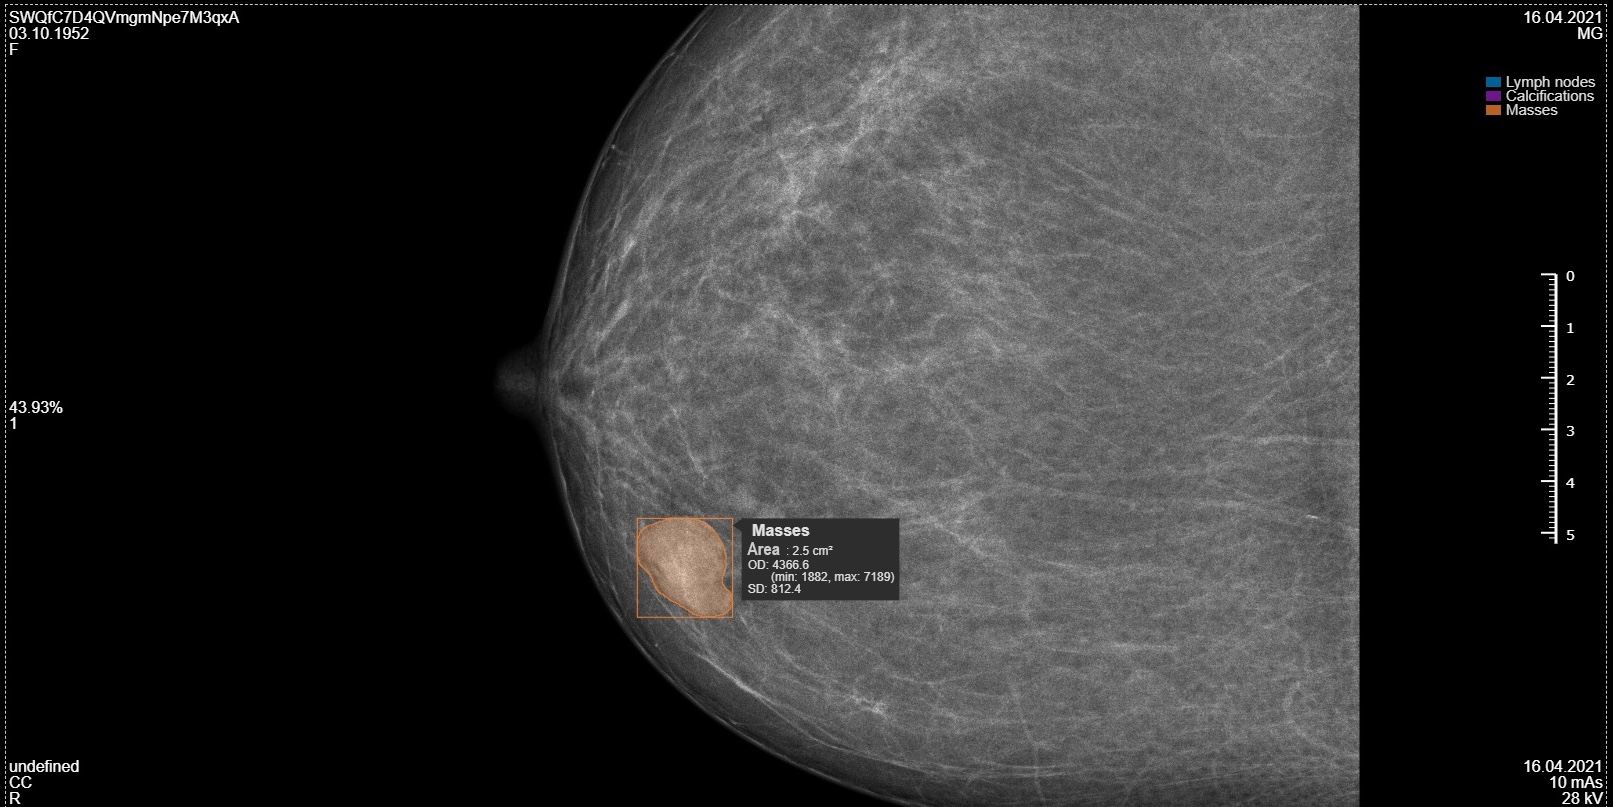

• Localizes pathologies with precise visual annotations on native mammogram images

• Performs quantitative analysis of detected elements, including their number and area